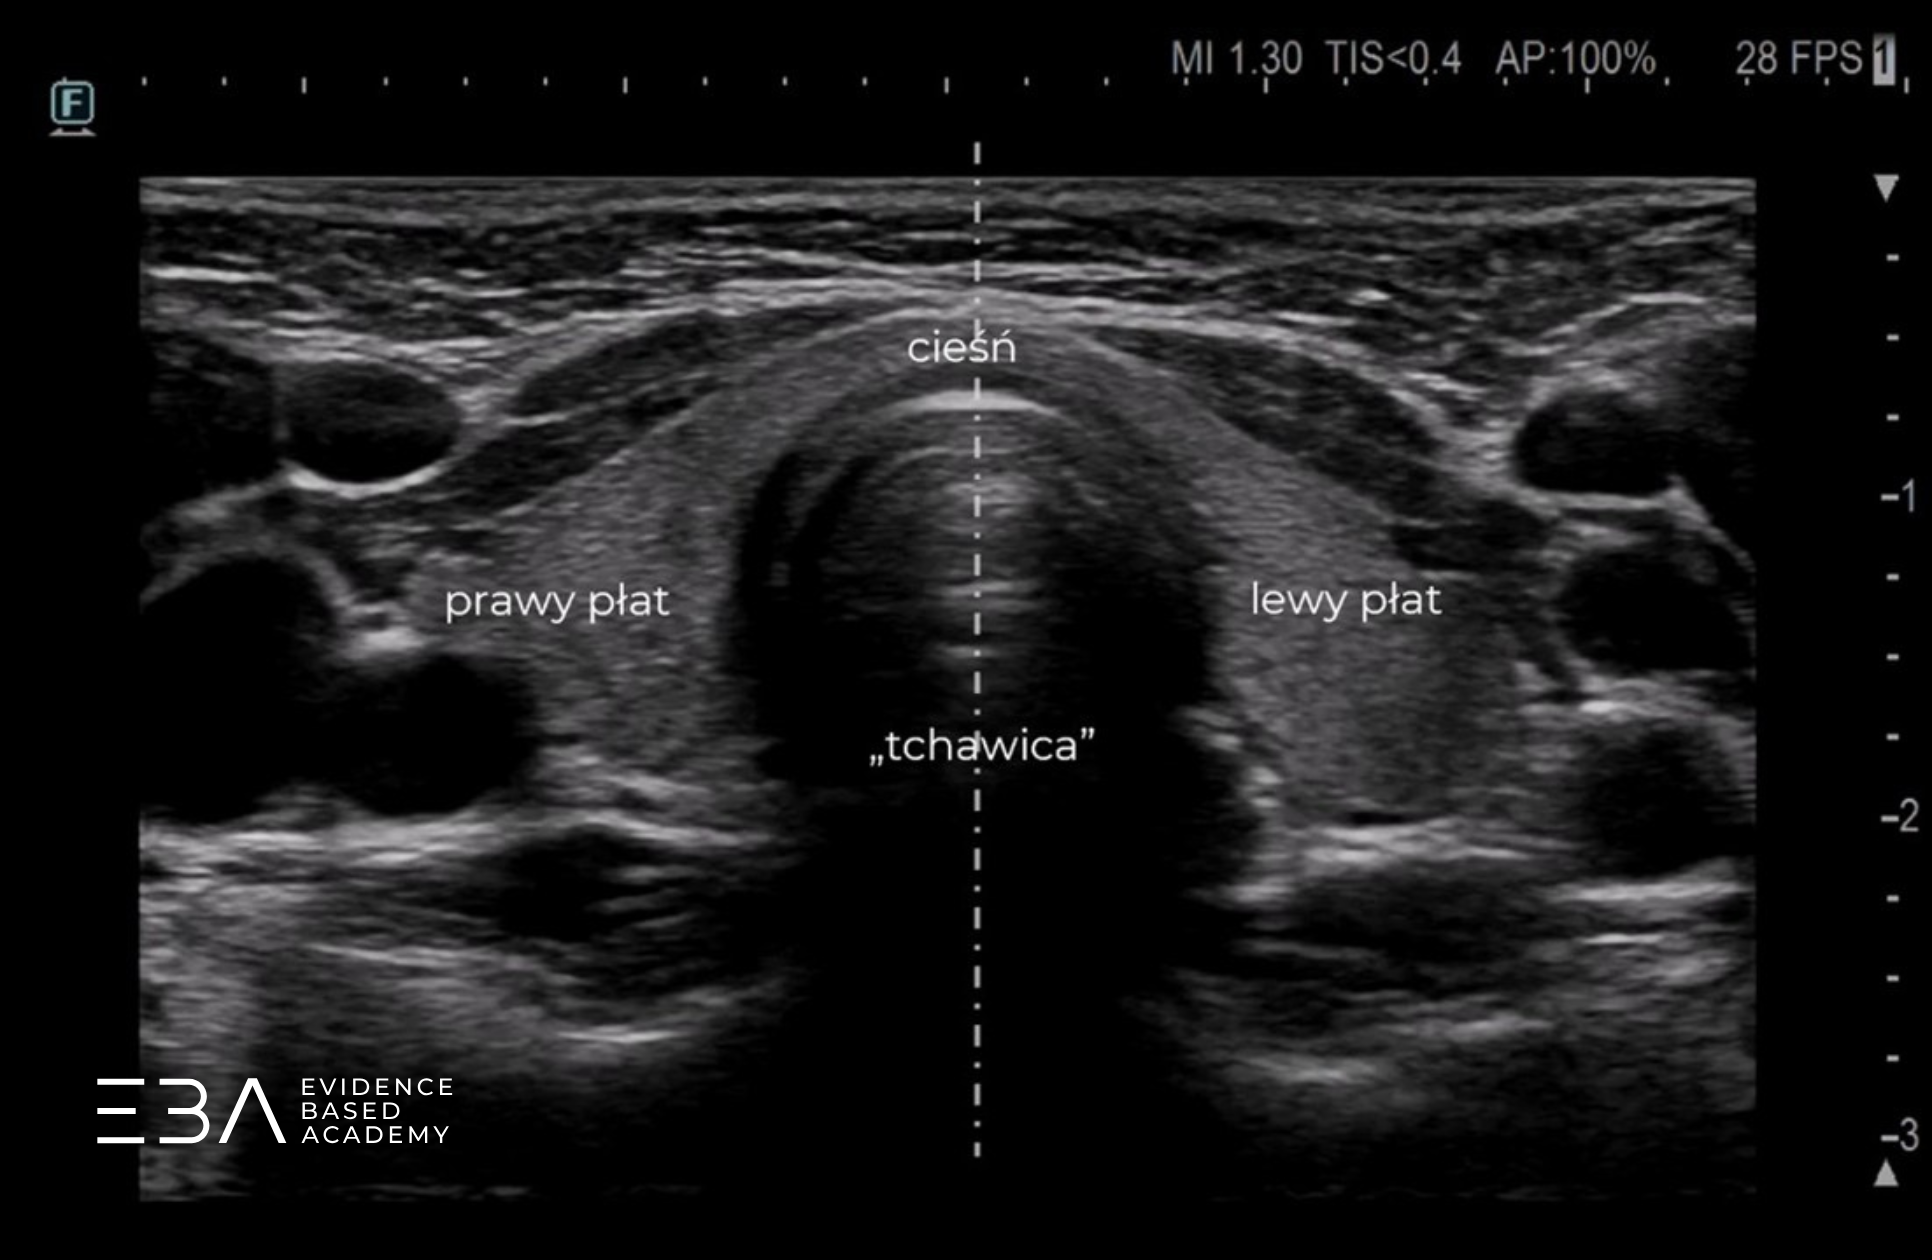

Ocenę miąższu tarczycy rozpoczynamy w projekcji poprzecznej, przykładając głowicę nieco poniżej krtani. Pamiętamy o właściwej pozycji znacznika na ekranie (po stronie naszej lewej ręki). Na tak uzyskanym obrazie po lewej stronie widzimy prawy płat tarczycy, pośrodkowo – cieśń, a po prawej stronie – płat lewy.

Przyłożenie głowicy poprzecznie pośrodkowo.

Skupiając się na jednym z płatów w przekroju poprzecznym, możemy podzielić go na części: brzuszną (przednią), grzbietową (tylną), boczną (przynaczyniową) oraz przyśrodkową (przytchawiczą).

Projekcja poprzeczna z podpisami omawianych struktur.